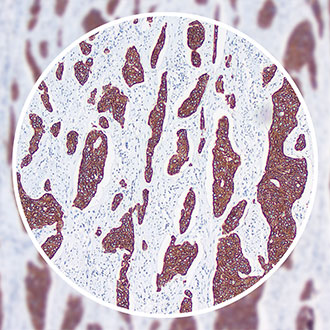

CK5&6

定位:细胞浆

阳性对照:扁桃体

CK5&6(Cytokeratin 5&6),分子量58 kDa及56 kDa,主要表达在鳞状上皮、导管上皮基底细胞、肌上皮细胞和间皮细胞中。CK5&6抗体可用于诊断鳞癌、基底细胞乳头状瘤、移行细胞癌和淋巴上皮癌,并可与其他特异性标记联用用于鉴别良恶性肿瘤。